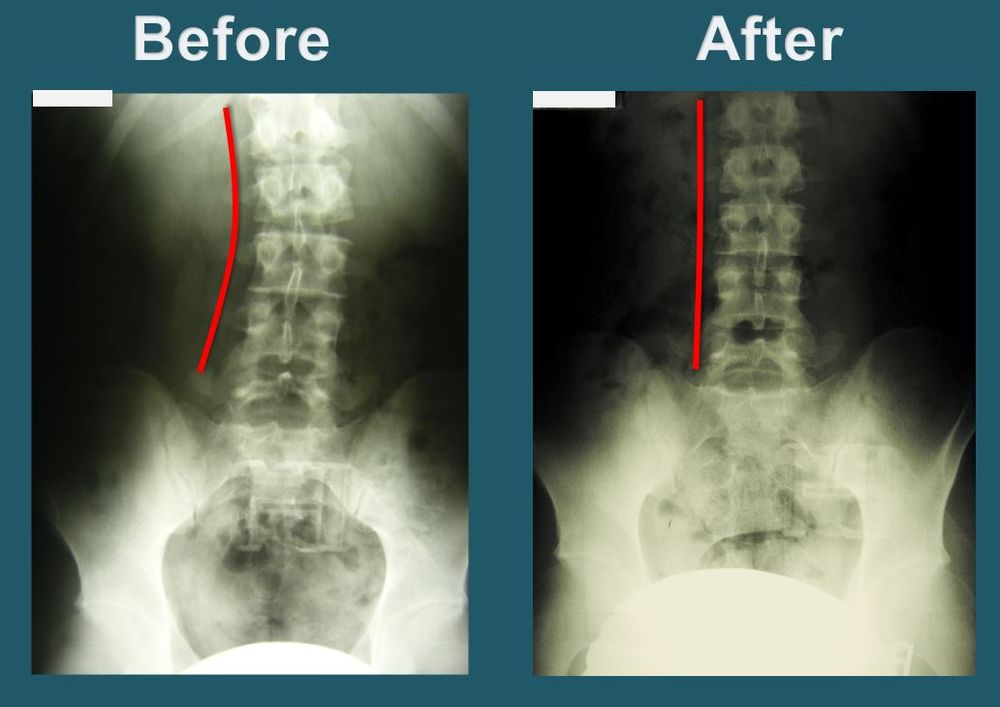

Dr. Park will take X-rays of the upper cervical region, neck, full spine, and pelvis to observe and examine the degree of misalignment. The doctor will then implement the procedure to restore head, neck and spinal alignment. This procedure is performed by the doctor’s own hands, without the use of any needles or electric therapy.

As soon as the vertebrae is aligned correctly, the brain will immediately start sending healing messages to those parts of the body affected by the misalignment and begin the natural self-healing process. Blockage of brain to body messages can be the direct or indirect cause of most health problems. On each visit, Dr. Park seeks to regain and maintain the proper alignment of the spine, aiding each patient through the process of recovery and healing.